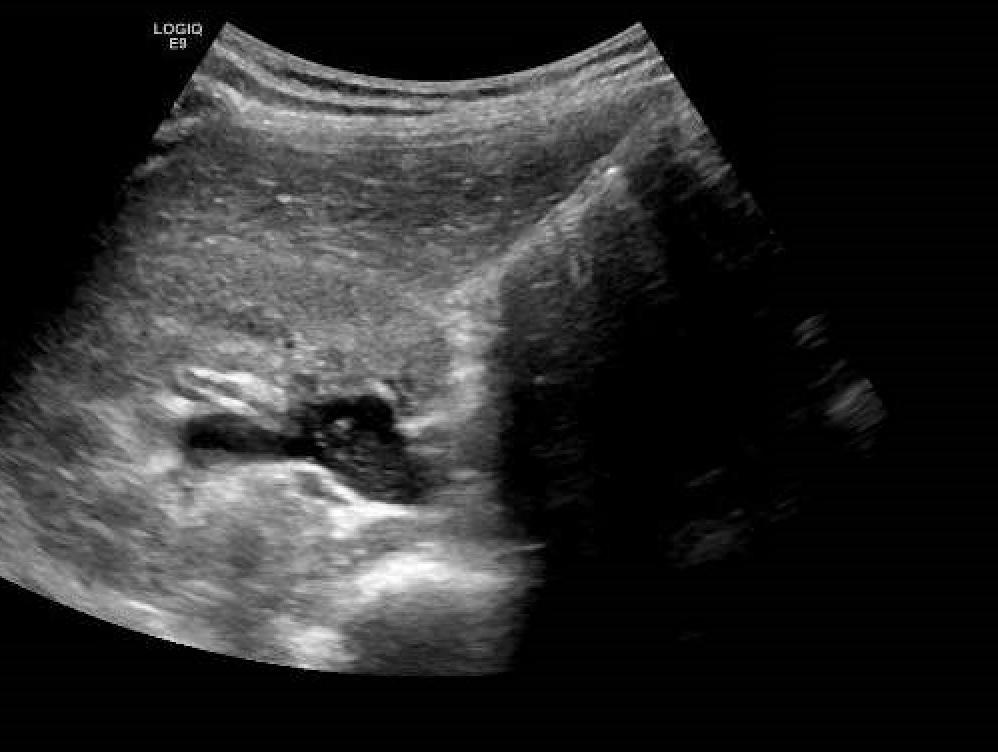

Hallazgos ecográficos

Juicio clínico: Hidronefrosis moderada por compresion uterina (embarazo).

La hidronefrosis en el embarazo, suele aparecer hasta en un 90%, sin embargo solo un pequeño porcentaje presenta clínica (3%). Aparece en la segunda mitad de la gestación, siendo las causas extrinsecas las más habituales (compresión por aumento de las vena ovaricas y/o uterino). En la actualidad, sigue siendo la ecografía el mejor metodo para su diagnóstico por su inocuidad. En la mayoría de los casos, solo precisa tratamiento sintomático, hidratación y medidas posturales maternos (decubito lateral sobre el lado contrario al del riñón dilatado con intención de disminuir la compresión por el utero).